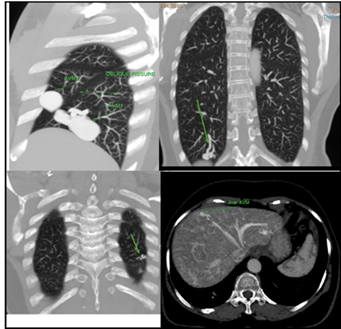

A Computed Tomography (CT)

Pulmonary angiogram (Figure 3) was suggested which confirmed the presence of 4 well defined

pulmonary arteriovenous malformations, three in the right lung, of which 2 were

in the lower lobe largest measuring 5.6 x 2.2 cm and one in the middle lobe

measuring 2.3 x 2.5 cm and one in the left lung. All AVMs were having single

arterial feeders (fistulous point). Two liver AVMs were also identified one

each in the right and left lobes.

Figure 3: (A):- Reconstructed CT

Sagittal image shows two

pulmonary AVMs in the right lung; one in lower lobe and other in middle lobe.

(B):- Reconstructed CT

coronal image shows third pulmonary AVM in the lower lobe of right lung.

(C):- Reconstructed CT

coronal image shows fourth pulmonary AVM in the lower lobe of left lung.

(D):- Reconstructed CT axial

image shows a hepatic AVM in the right lobe of the liver.